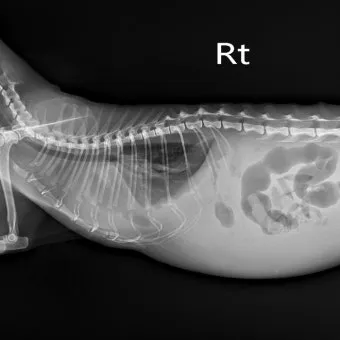

교통사고나 높은 곳에서 떨어졌을 때 발생하는 외상성 복막염도 무시할 수 없어요. 복부에 강한 충격이 가해지면 내장 기관이 파열되거나 혈관이 터지면서 복강 내 출혈이 시작되거든요.

이때는 출혈성 복막염이 발생하는데, 혈액 자체가 복막을 자극해서 염증을 일으켜요. 특히 비장이나 간 같은 혈관이 풍부한 장기가 손상되면 대량 출혈로 이어질 수 있어서 정말 위험해요.